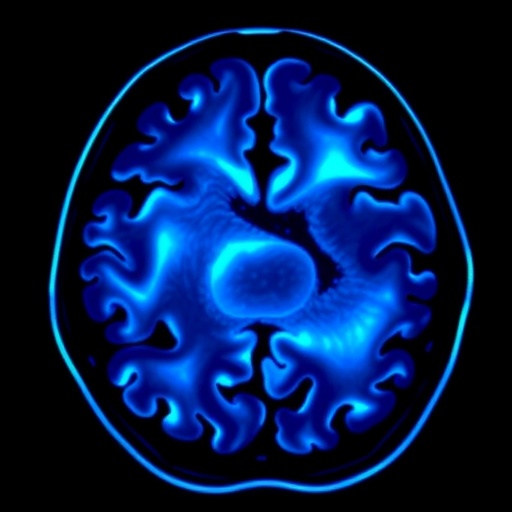

Through high-resolution fetal neurosonography, the researchers meticulously assessed cortical sulcation—the complex patterning of brain grooves and ridges that govern cognitive and motor functions—and the architecture of midline brain structures, including the corpus callosum and the cavum septi pellucidi. The sulcation process is a key developmental milestone in utero, with deviations often indicative of impaired neuronal migration or cortical organization. The study’s findings demonstrated that LO-FGR fetuses exhibited a statistically significant delay and simplification in cortical folding compared to both SGA and AGA groups, suggesting a unique neuropathological signature.

The delineation of midline brain structures further enriched the clinical narrative. The corpus callosum, a pivotal commissural fiber tract enabling interhemispheric communication, was notably thinner and less developed in the LO-FGR cohort. Given that the corpus callosum continues to develop well into the third trimester, these findings imply that late gestational stressors inherent to LO-FGR disrupt crucial neurodevelopmental windows, potentially predisposing to cognitive and behavioral sequelae.

Moreover, the study delineated subtle disparities in the cavum septi pellucidi morphology, a transient fetal structure whose anomalies have been implicated in neuropsychiatric disorders. These architectural deviations, though nuanced, underscore the vulnerability of midline structures to impaired growth and oxygenation, thus emphasizing the need for refined fetal brain surveillance protocols in suspected LO-FGR cases.